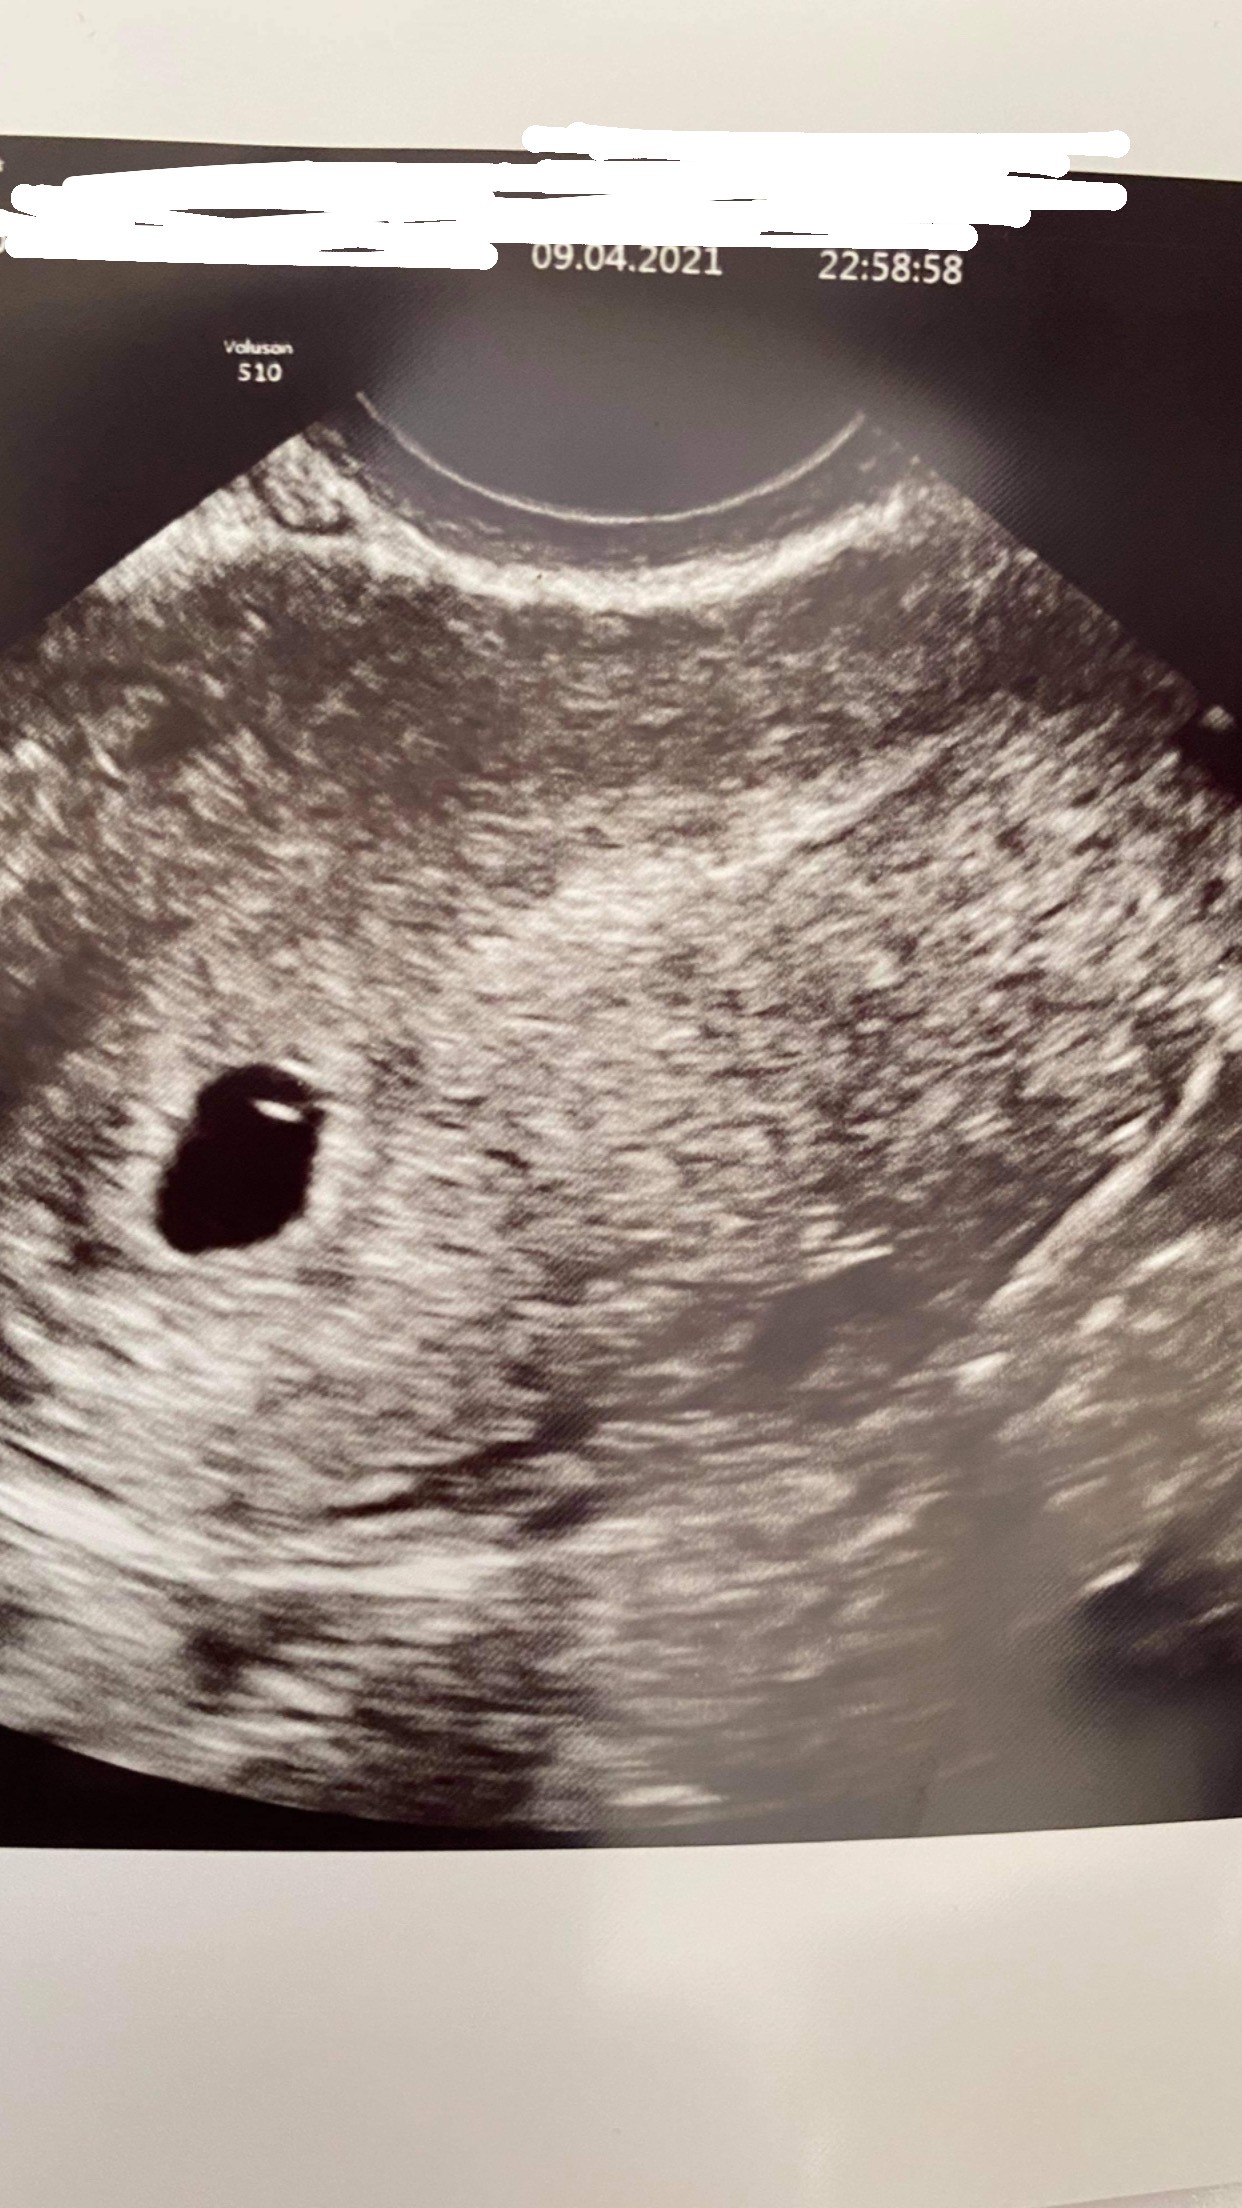

Byłam na usg. Jest pęcherzyk i żółtkowy też. Także jestem spokojniejsza o 200%

Ja też byłam 9.04 i USG podobne następna wizyta 23.04 i powinno być już serduszkoTo usg sprzed 2 tyg myślicie ze będzie widać w niedziele coś więcej ? nie wiem czy nie poczekać może jeszcze chwile

Napisz mi jak po wizycie i co było widoczne ja mam 25Ja też byłam 9.04 i USG podobne następna wizyta 23.04 i powinno być już serduszko![]()